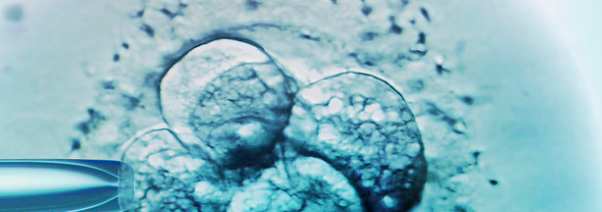

卵胞浆内单精子注射(ICSI)

目前,西班牙社保为不能生育子女的夫妇(仅覆盖39岁以下的女性)提供三次辅助助孕的尝试。 接受治疗的平均年龄在35-39之间。但不包括最为昂贵的一些先进技术,未来的爸爸妈妈们大部分都需要去私立医院接受治疗。对比第一代试管婴儿技术(路易斯使用的),欧洲医院更青睐卵胞浆内单精子注射(ICSI)。这个技术允许选择精子,这样就可以选择“长得最漂亮最健康的”精子。ICSI是在20世纪90年代初开发的,作为男性不育的特定治疗方法(精子数量低,精子质量低),是第二代试管婴儿技术。